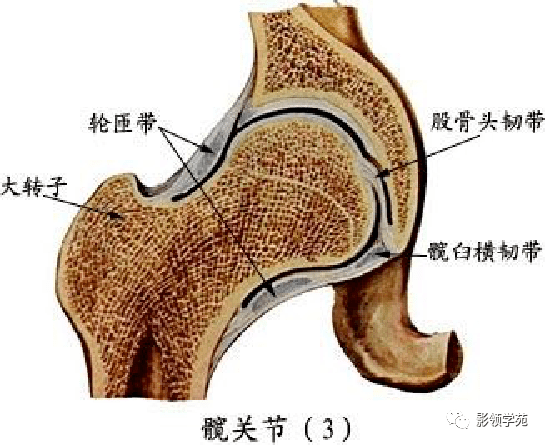

关节与韧带系统

韧带系统

关节与韧带系统

韧带系统